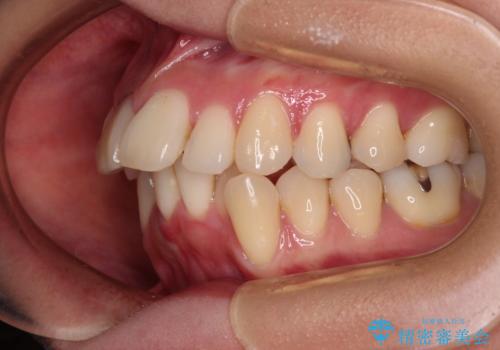

- 八重歯と上の前歯が出っ歯になっていることを気にして来院された患者様です。

横から見た際の口元の飛び出した印象も改善したいとのことで、上下左右の第一小臼歯4本を抜歯し、ワイヤー装置にて抜歯矯正を行うこととしました。

前歯の変色している歯は、神経組織が壊死していたため、矯正治療前に根管治療を実施し、矯正治療後にオールセラミッククラウンにて補綴治療を行うこととしました。